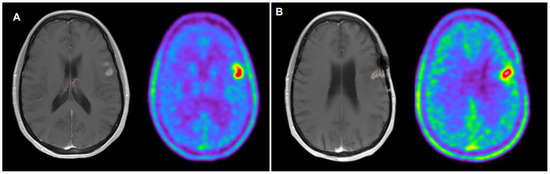

- Ceccon, G.; Lohmann, P.; Werner, J.M.; Tscherpel, C.; Dunkl, V.; Stoffels, G.; Rosen, J.; Rapp, M.; Sabel, M.; Herrlinger, U.; et al. Early treatment response assessment using 18F-FET PET compared with contrast-enhanced MRI in glioma patients after adjuvant temozolomide chemotherapy. J. Nucl. Med. 2021, 62, 918–925. [Google Scholar] [CrossRef] [PubMed]

- Wollring, M.M.; Werner, J.M.; Bauer, E.K.; Tscherpel, C.; Ceccon, G.S.; Lohmann, P.; Stoffels, G.; Kabbasch, C.; Goldbrunner, R.; Fink, G.R.; et al. Prediction of response to lomustinebased chemotherapy in glioma patients at recurrence using MRI and FET PET. Neuro Oncol. 2023, 25, 984–994. [Google Scholar] [CrossRef] [PubMed]

- Galldiks, N.; Langen, K.J.; Holy, R.; Pinkawa, M.; Stoffels, G.; Nolte, K.W.; Kaiser, H.J.; Filss, C.P.; Fink, G.R.; Coenen, H.H.; et al. Assessment of treatment response in patients with glioblastoma using O-(2-18F-fluoroethyl)-L-tyrosine PET in comparison to MRI. J. Nucl. Med. 2012, 53, 1048–1057. [Google Scholar] [CrossRef]